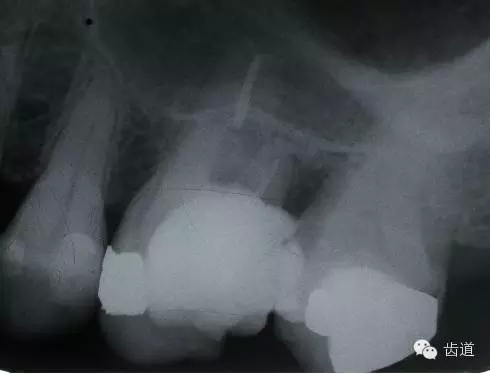

磨牙髓室頂、底距離接近時(shí),易將髓底穿孔。

左下6底穿

左上6底穿

左上7近中頰根器械折斷

右上6腭根器械折斷